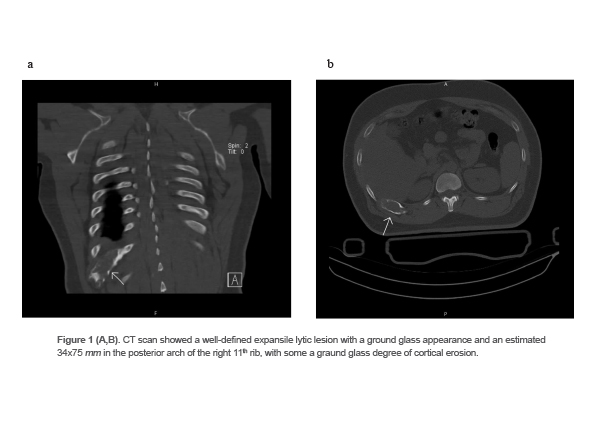

A 32-year-old man was referred to the radiology department with a complaint of a prolonged cough after an accident. The CT scan showed a well-defined expansile lytic lesion with a ground glass appearance and an estimated 34x75 mm in the posterior arch of the right 11th rib, with some degree of cortical erosion. The differential diagnoses in imaging were fibrous dysplasia, lymphoma and metastasis (Figures 1A and 1B). Due to the uncertainty of the diagnosis, a core needle biopsy of the lesion was taken. The specimen consisted of multiple pieces of bony tissues measured together 1×0.1 cm. The histological examination showed bone trabeculae with tumoral lesion composed of spindle-shaped fibroblasts in storiform arrangement admixed with multiple osteoclast-like multinucleated giant cells and hemosiderin deposition and few inflammatory cells (Figures 2A and 2B). Based on the imaging and H&E studies, non-ossifying fibroma of rib was confirmed.

Figure 1 (A,B). CT scan showed a well-defined expansile lytic lesion with a ground glass appearance and an estimated 34x75 mm in the posterior arch of the right 11th rib, with some a graund glass degree of cortical erosion.